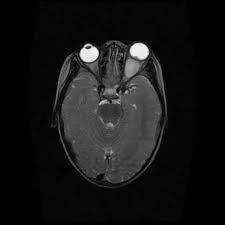

Symptoms of an optic nerve glioma are caused by the tumor pressing against the nerves. Common symptoms of this kind of tumor include: nausea and vomiting balance problems vision disturbances headaches Other symptoms can include: involuntary eye movements memory impairment daytime sleepiness loss of appetite growth delays Hormone problems may also appear because the tumors can occur near the base of the brain where hormones are controlled.